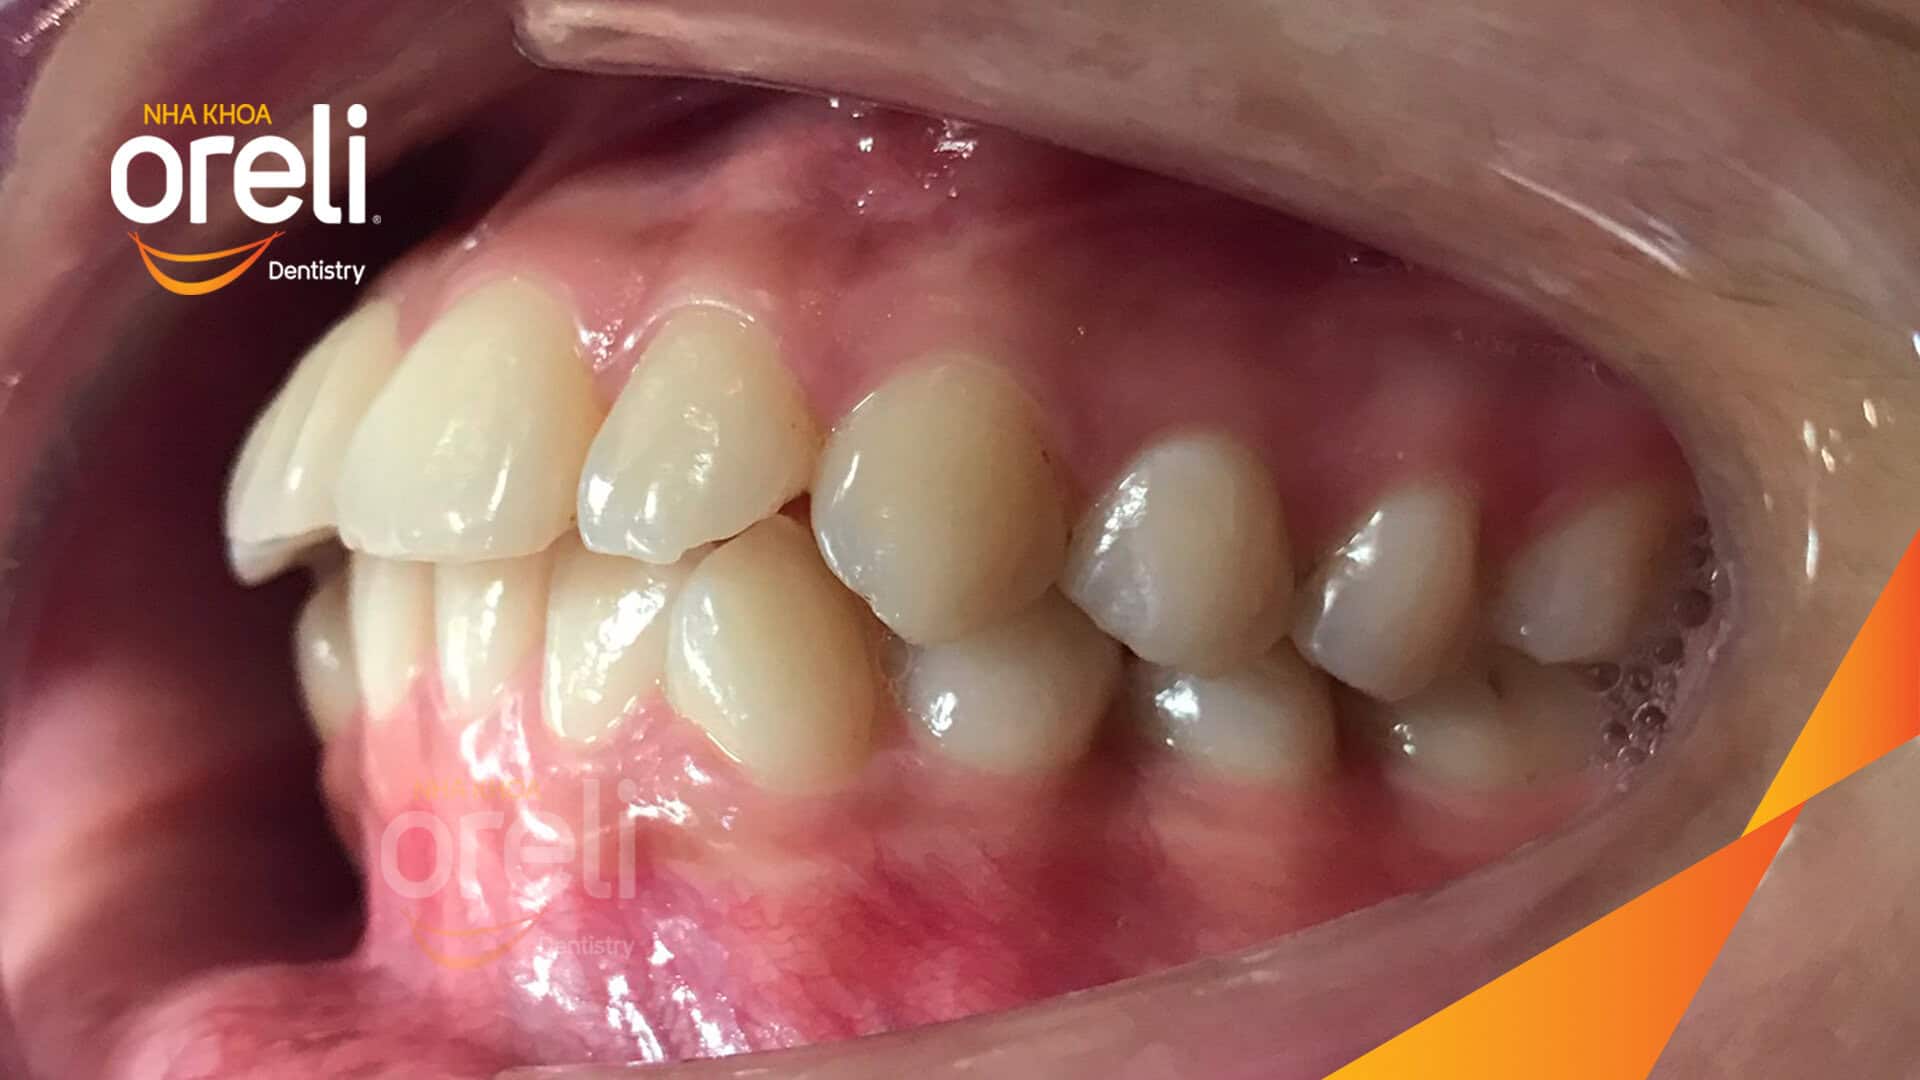

Kết quả: Khớp cắn đúng nụ cười tự nhiên, góc mặt nghiêng đẹp

Răng số 4 là răng ít chức năng hơn so với các răng khác trên cung hàm, trên phương diện thẩm mỹ răng số 4 trùng với răng số 5 theo chiều trước sau. Do vậy việc nhổ răng 4 hoặc răng số 5 trong chỉnh nha để nắn chỉnh răng hô thường được lựa chọn.